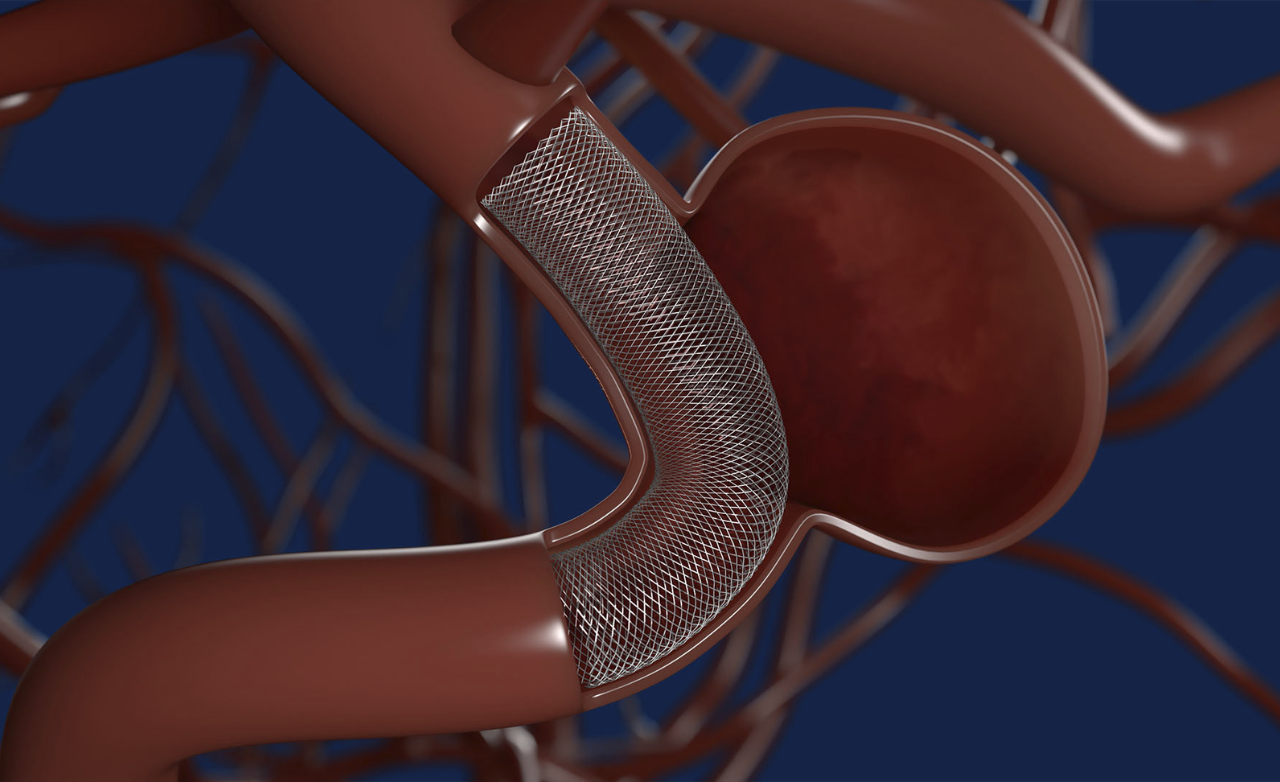

A bulging, weakened blood vessel in the brain that may rupture, causing life-threatening bleeding, headaches, neurological deficits, or stroke.

Minimally invasive technique using soft coils to block aneurysm flow, preventing rupture and ensuring long-term vascular stability.

Provides support for wide-neck aneurysms, ensuring secure coil placement and safer, more effective treatment.

Enhances treatment by redirecting blood flow away from the aneurysm, promoting gradual healing, improving vessel stability, and ensuring stronger, durable protection against future rupture.